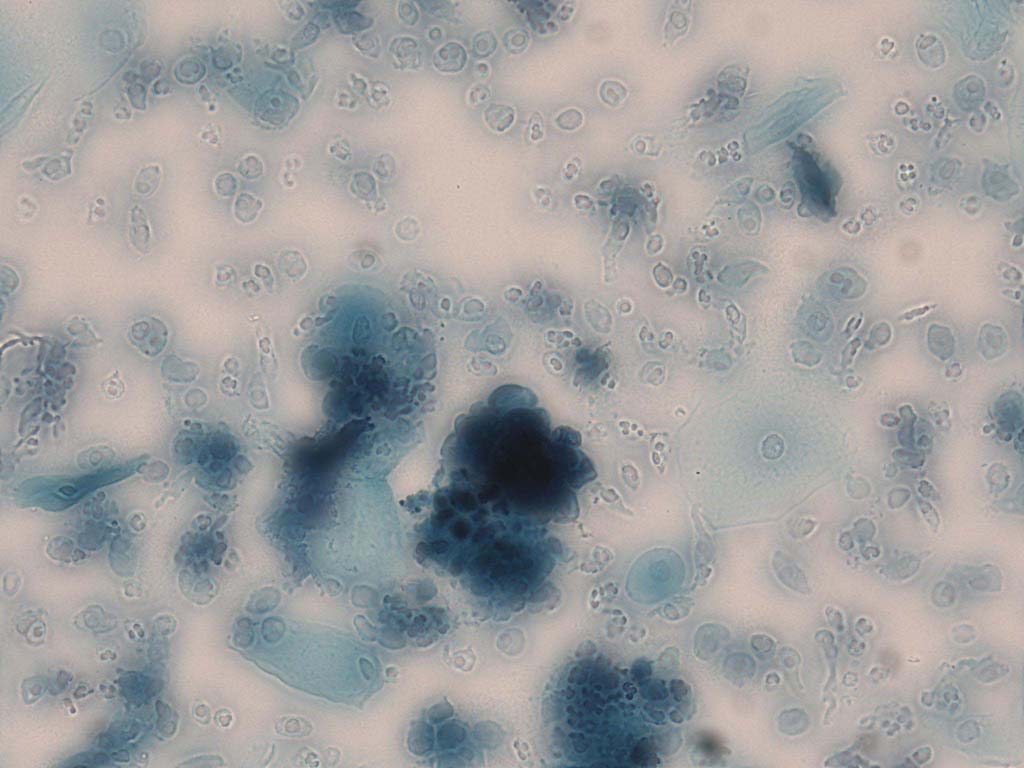

To demonstrate the effectiveness and efficiency of the proposed image fusion method , we conduct a set of comparative experiments on three image datasets. The first is composed by 8 pairs of multi-modal medical images and the second one contains 15 pairs of multi-focus gray or color natural images. These two datasets are often used in many related papers and some examples are shown in Figure 3(a) and Figure 3(b). The third one is a new multi-focus cervical cell image dataset collected by ourselves, which consists of 15 groups of color images and each group contains a series of multi-focus cervix cell images with size of or , etc. Some source examples are shown in Figure 3(c). Our source code implemented in C++ along with the new multi-focus cervical cell image dataset is available online.

Figure 9, Figure 10 and Figure 11 show the comparative fused results of the multi-focus cell images shown in Figure 3(c). For clarity, we also present a closeup view in the right-bottom of each sub-picture in Figure 9 and Figure 10. As shown in the close-up views of Figure 9, the fused images based on DSIFT, IM, MWGF and BF methods are extremely blurred in the boundary and fail to keep the details of cell nucleus. Furthermore, the DTCWT and NSCT based methods produce halo artifacts in the fused images, while GFF and CNN based methods fail to preserve the small cell nucleus. LP-SR based method nearly works fine which keeps the most of the details of the small size cells, but the integrity of the clustered large size cells is damaged. Fortunately, in our proposed method, the integrity of the clustered large size cells is preserved and most of the isolated small size cells are maintained from the original images, which demonstrates the best visual quality.

Similarly, as shown in the close-up views of Figure 10, the fused images from DSIFT, IM, MWGF and BF are blurred and lose some nucleus details, while the results from DTCWT, GFF, CNN and NSCT produce halo artifacts. LP-SR based method can keep details well but also produces halo artifacts and other noise. Our method can preserve the focused areas of different source images well without introducing any artifacts. For the example illustrated in Figure 11, the fused images generated by DSIFT, DTCWT, IM and NSCT all fail to preserve the focused areas of different source images and result in extremely blurred images. The GFF, CNN, MWGF and BF based method introduces a lot of color distortion of the nucleus regions and the obvious halo artifact. The result of LP-SR based method is close to the one of our method but introduces some odd color distortion. Again, our method produces fused image which can preserve the focused areas of different source images well without introducing any artifacts.